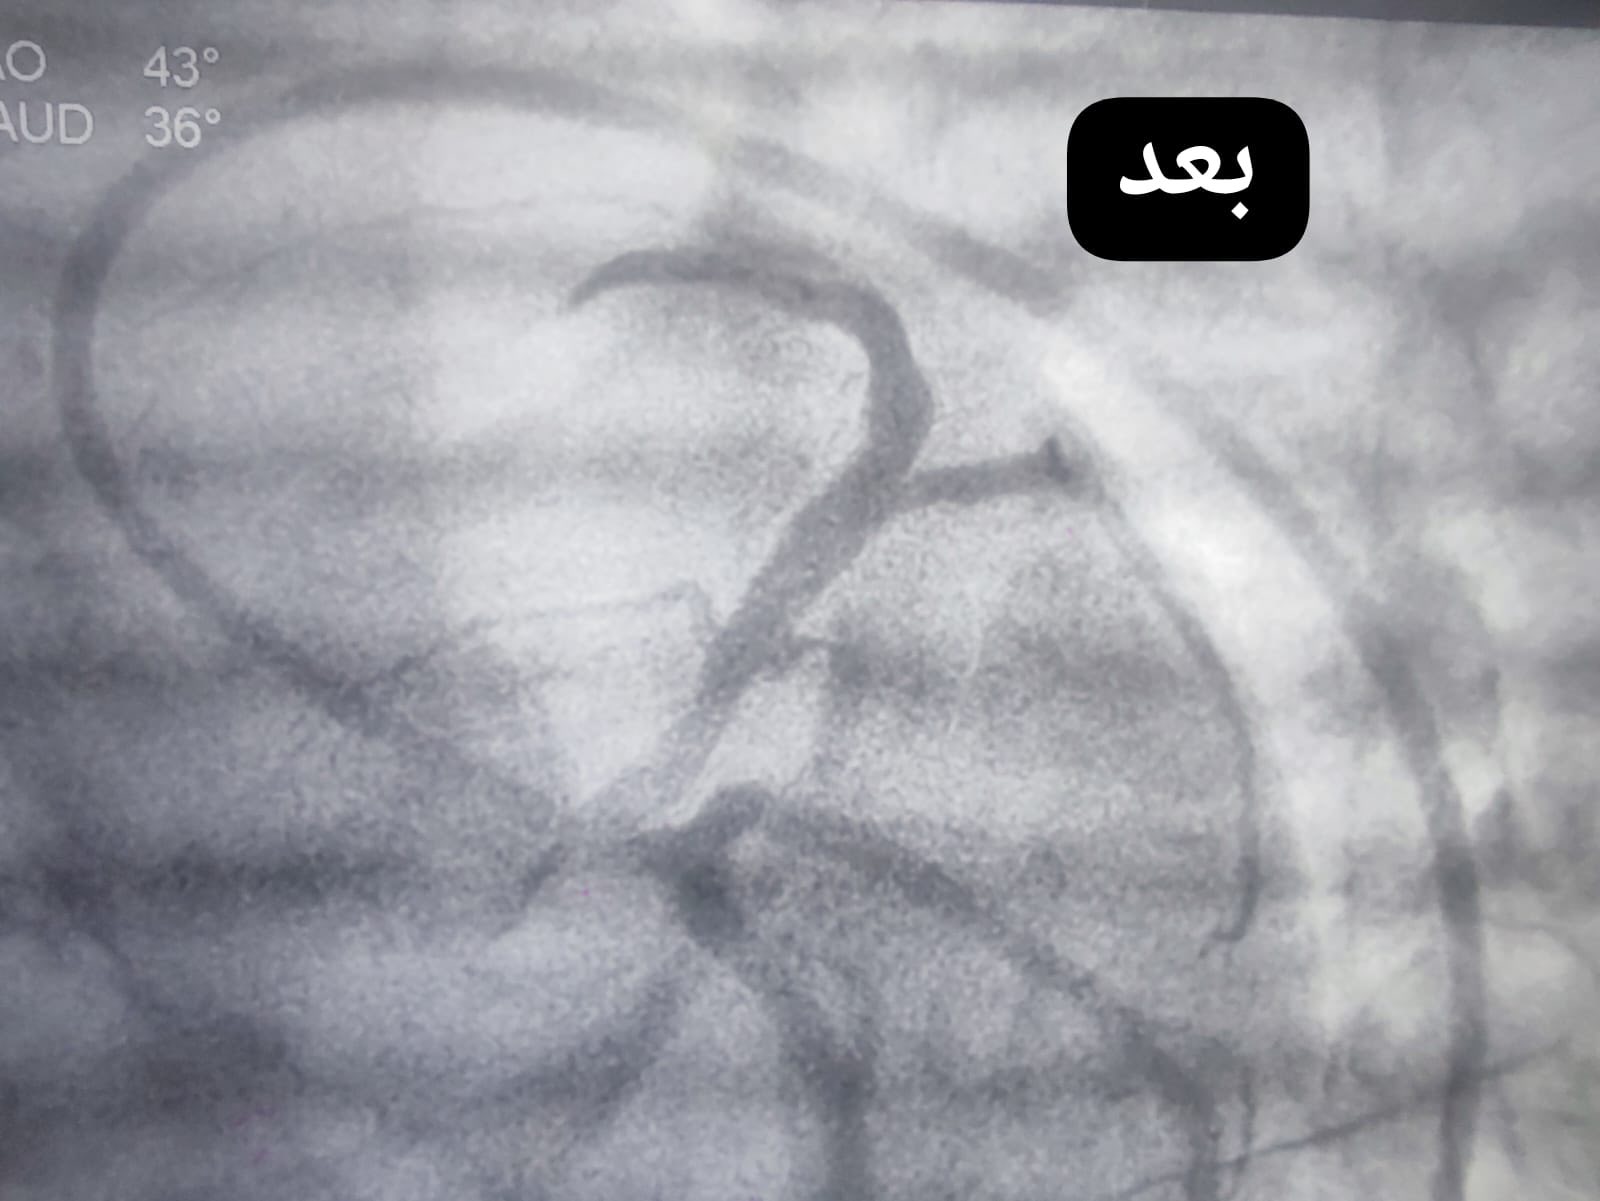

وفي هذا السياق، استقبلت الوحدة حالة حرجة لفتاة في مقتبل العمر، حيث أظهرت الفحوصات ورسم القلب إصابتها بجلطة حادة مع انسداد كامل في الشريان التاجي الأمامي الرئيسي، وهو ما استدعى التدخل الفوري لإنقاذ حياتها.

وعلى الفور، باشر فريق الإنعاش التعامل مع الحالة، وتمكن من إعادة النبض بنجاح، لتُجرى بعدها قسطرة قلبية علاجية عاجلة، أسفرت عن فتح الانسداد في الشريان التاجي الأمامي الرئيسي بنجاح تام.

وأسفر التدخل السريع عن تحسن ملحوظ في وظائف القلب، واستقرار الحالة الصحية للمريضة، التي غادرت المستشفى بعد أيام قليلة في حالة جيدة.